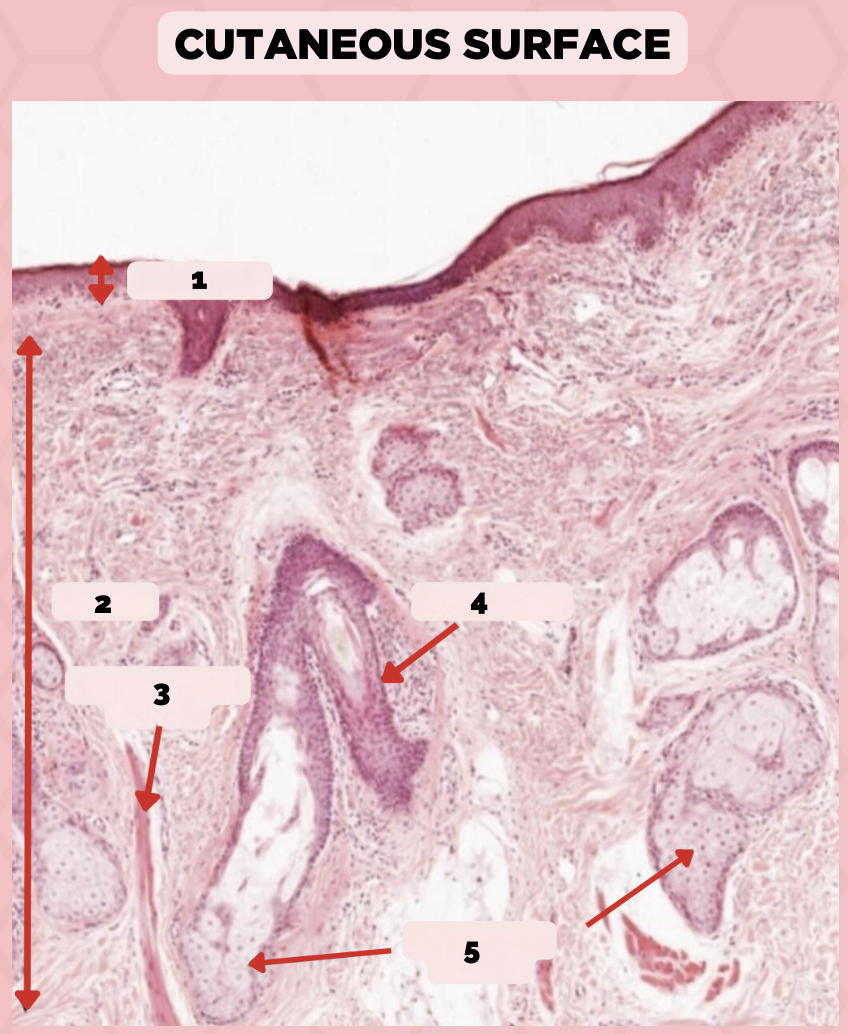

Lip

What is the specimen showed in the picture?

Epidermis

Identify the structure labeled as 1.

Dermis

Identify the structure labeled as 2.

Arrector Pilli Muscle

Identify the structure labeled as 3.

Hair Follicle

Identify the structure labeled as 4.

Sebaceous Glands

Identify the structure labeled as 5.